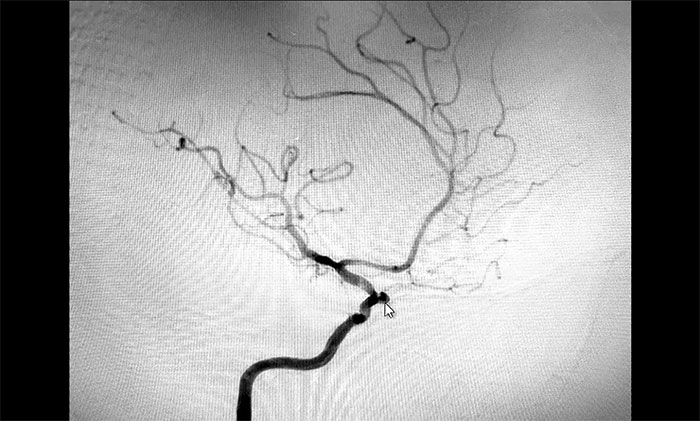

考慮腦出血后遺癥可能,于耀宇主任為秦女士完善相關(guān)檢查。通過DSA全腦血管造影檢查,發(fā)現(xiàn)患者右側(cè)頸內(nèi)動脈眼動脈段動脈瘤形成,瘤囊直徑約3mm,就像一顆長在動脈血管上的“葡萄”,里面充盈流淌著血液。

▲ DSA檢查發(fā)現(xiàn)顱內(nèi)動脈瘤